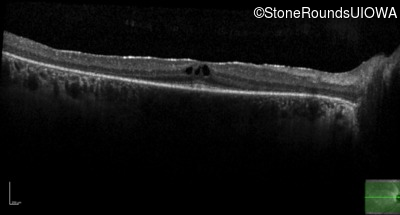

Optical Coherence Tomography - Left -

20/20 -2

Exemplar / OCT Stack

OCT Stack